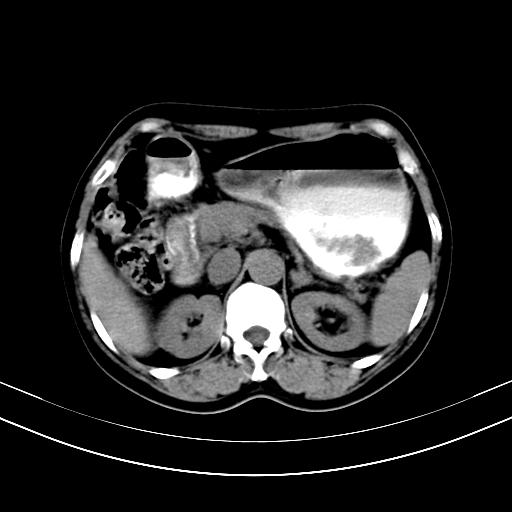

标题: CT12767:肝脏病变请会诊

补充强化片

胃内见充盈缺损,建议行胃镜病理检查,如果胃内无占位,则肝内考虑左叶、尾叶为包膜型肝癌,如有则考虑为转移瘤

胃内的充盈缺损,当时让患者俯卧位在扫描一下就 好了,当然最好是增强扫描,肝脏的病灶平扫很难定性,可以考虑是肝癌·血管瘤·转移瘤!

胃内见充盈缺损,建议行胃镜病理检查,如果胃内无占位,则肝内考虑左叶、尾叶为包膜型肝癌,如有则考虑为转移瘤,左侧肾上腺 明显增大,成结节改变,本人考虑转移瘤可能性大。

胃内的充盈缺损因胃壁不厚,我个人考虑为胃内残留物。肝左叶及尾叶病灶,我首先考虑血管瘤,其次为肝癌。(尾叶的更低密度区太规整)

肝脏左叶和尾叶均见略低密度影,尾叶病变内见坏死?其边界清晰,形态规整1血管瘤,2肝癌待排

1.肝左叶及尾叶占位建议增强2.肝硬化

肝脏左叶和尾叶均见略低密度影,尾叶病变内见坏死?其边界清晰,形态规整1血管瘤,2肝癌待排3建议增强。

胃内充盈缺损考虑为胃内存留物,肝左叶和尾状叶两个病灶,均为低密度,建议增强。

考虑:胃体小弯侧胃癌(或平滑肌瘤恶化或平滑肌肉瘤)伴肝转移,左侧肾上腺转移不除外.

胃内充盈缺损考虑为肿瘤,肝尾叶及左叶肿块考虑转移瘤

胃癌肝内转移及肾上腺转移。

胃窦部占位伴肝及左肾上腺转移可能大,建议增强扫描。

肝脏左叶和尾叶均见略低密度影,尾叶病变内见坏死?其边界清晰,形态规整1血管瘤,2肝癌待排3建议增强或结合临床及超声与实验室检查

肝左叶及尾叶低密度灶,增强有渐进性明显强化,考虑血管瘤。胃内“充缺”首先要排除异物(食物),变换体位可鉴别。增强时机抓的不好,还应该有延时像。

谢谢楼主的增强片子,平扫没发现左侧肾上腺的问题很不好意思,可惜片子只有门脉期,所以还只有猜,肝脏的病灶在门脉期部分强化,首先考虑为血管瘤(其他的用一种病不好解释)胃要喝水就好了现在不好说是否有问题,左肾上腺的问题考虑是肿瘤。

做了增强后,可以明确胃是没有肿瘤的,肾上腺也没有肿瘤.肝左叶的病灶首先考虑血管瘤,应该再延迟,肝尾状叶的病灶仍不能排除肝癌的可能性.